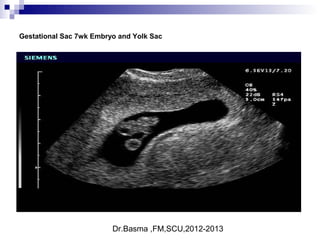

Gestational Sac 7wk Embryo and Yolk Sac

Dr.Basma ,FM,SCU,2012-2013